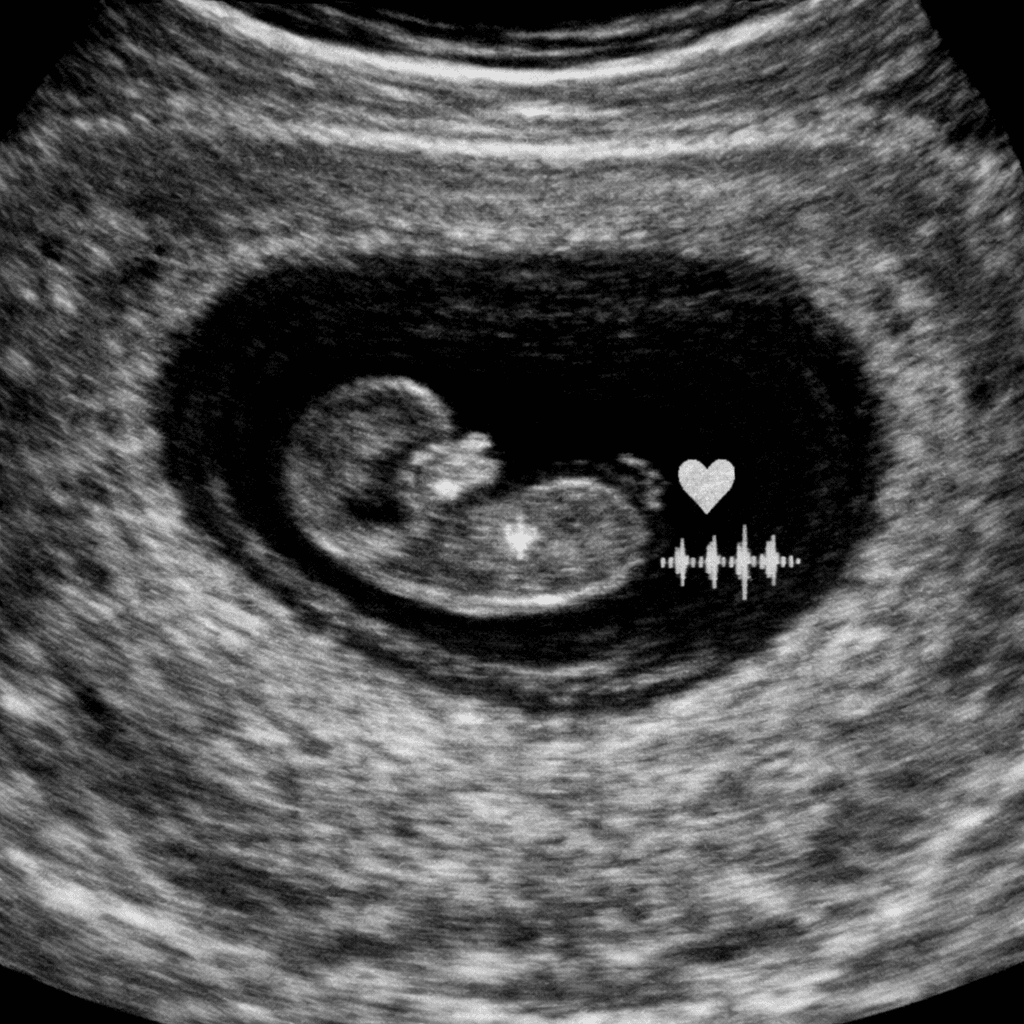

Vitaliteitsecho

Wanneer je net ontdekt dat je zwanger bent, begint er een bijzondere periode. Vaak is die eerste fase ook spannend. Je wilt graag weten of de zwangerschap zich goed ontwikkelt, of het hartje klopt en of alles op de juiste plek zit. Een vitaliteitsecho kan in deze vroege weken veel duidelijkheid en rust geven. Wat […]